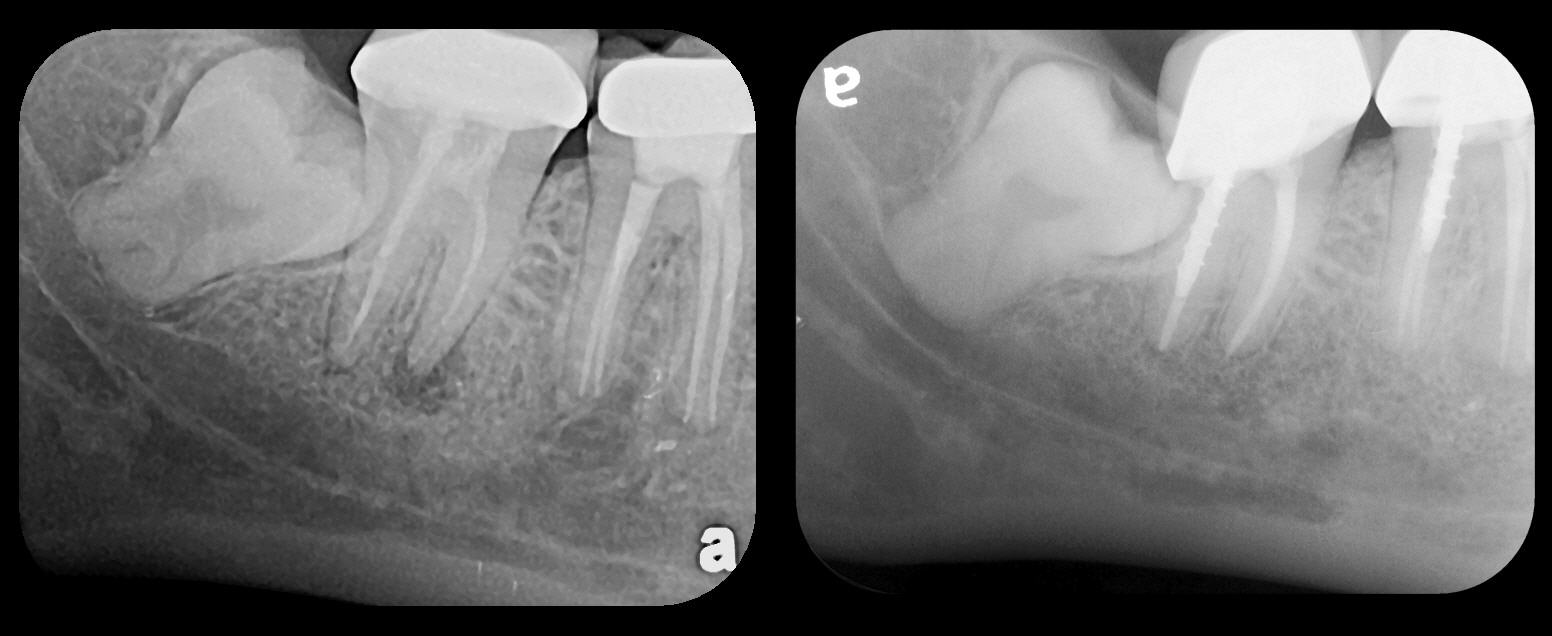

Fig 4. Severe dilaceration of root of tooth No. 17 and

curvature of roots of No. 18. Mandibular canal and inferior border of mandible are

easily visualized. If extraction of No. 17 is planned, a 3D CBCT study is required

due to proximity of tooth root to vascular and inferior alveolar nerve contents of

mandibular canal and possibility of surgical complications.

Figure 4

Fig 5. Bilateral concerns for this patient are evident on these PSP

radiographs. Tooth No. 17 may exhibit pathology distal to the root. In

addition, extreme length of root of tooth No. 32 through the entire height

of the body of the mandible is cause for concern if extractions of Nos.

17 and 32 are planned. Three-dimensional CBCT study and alerts to

the patient as to the potential surgical complications on extractions are

required in this instance. There is no benefit to panoramic radiography

in this case.

Figure 5

Fig 6. PA radiograph showing 90-degree dilacerations of

mesial and distal roots of tooth No. 32 and intersection of mandibular

canal with these roots. Extraction of tooth No. 32 requires 3D study, and

patient was advised as to this necessity.

Figure 6